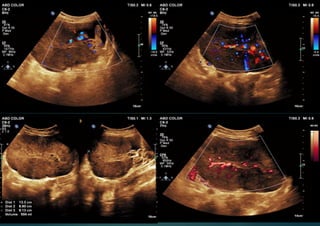

Stage 4 ovarian carcinoma with

ascites

Tumor with at least moderate blood flow, ascites, postmenopausal